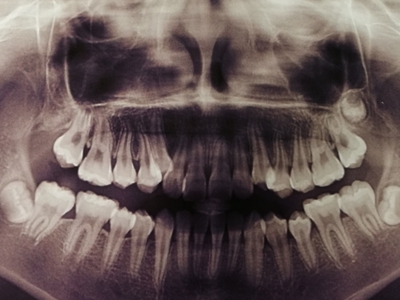

阻生牙是指由于邻牙、骨或软组织的阻碍而只能部分萌出或完全不能萌出,且以后也不能萌出的牙。引起牙阻生的成因,主要是由于颌骨缺乏足够的空间容纳全部恒牙。常见的阻生牙为下颌第三磨牙、上颌第三磨牙及上颌尖牙。

阻生牙主要原因是随着人类的进化,颌骨的退化与牙量的退化不一致,导致骨量相对小于牙量,颌骨缺乏足够的空间容纳全部恒牙。

对于阻生牙的处置需要首先明确阻生牙齿发育情况是否正常,对于由于早期外伤或其他原因造成发育异常,如牙根弯曲、短根等情况的阻生牙,还应根据患者的综合情况,决定牙齿是否保留。

发育正常的牙齿同时正畸治疗又不需要进行拔牙矫治,通常需要对阻生牙进行牵引治疗,引导进入牙弓,而对于发育异常的阻生牙加之正畸治疗需要进行拔牙矫治,通常可以考虑将阻生牙拔除,而避免再拔发育正常的前磨牙,即降低了正畸治疗的难度及不确定性,又保留了相对正常的牙齿。